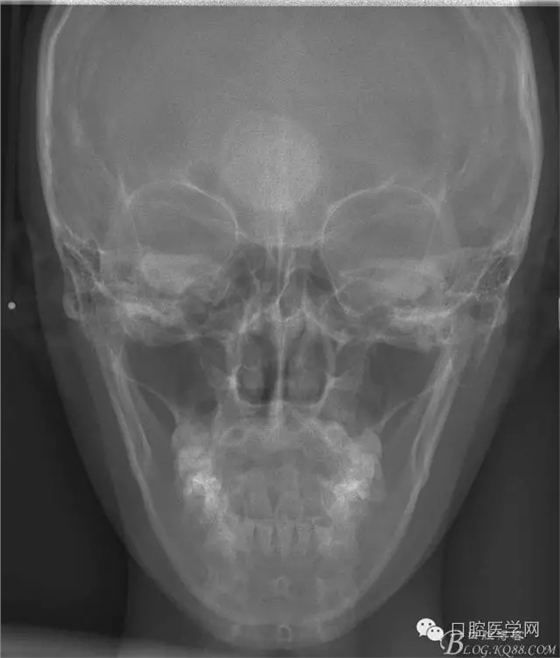

正畸查:替牙合。第一恒磨牙中性合。上牙弓尖圓型下牙弓方圓型。前牙覆合3度覆蓋7.5mm。下前牙咬到上舌側(cè)牙齦。上頜擁擠4.0mm,下頜擁擠

3.0mm。上頜稍前突下頜后縮,上下唇前突,上前牙覆蓋下唇,下唇外翻。面下三分之一過短,頦唇溝明顯,開唇露齒,頦饜窩明顯。顳下頜關(guān)節(jié)開閉口無彈響,無壓痛,開口型開口度正常。